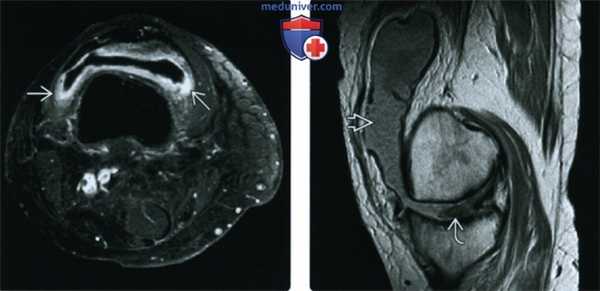

(Слева) Рентгенография в боковой проекции: признаки остеопении, наличия выпота в суставе и мягкотканного образования в заднем отделе без очевидной костной деструкции. Такая картина не является специфичной.

(Справа) МРТ, сагиттальная проекция, режим Т1 с подавлением сигнала от жира: визуализируется образование, представляющее собой скопление жидкости; МРТ в аксиальной проекции подтверждает, что это подколенная киста. Обратите внимание на утолщенную контрастированную стенку кисты, указывающую на наличие синовита, аналогично тому, который визуализируется в суставе. Определяются характерные для РА выраженное истончение хряща, небольшие эрозии и отек костного мозга.

о Переднее или заднее смещение большеберцовой кости (крестообразные связки)

(Слева) МРТ, аксиальная проекция, режим Т1, с контрастным усилением, с подавлением сигнала от жира: контрастируемая утолщенная синовиальная оболочка с подтвержденным синовитом, что не является специфичным и может иметь место при септическом артрите. При анализе аспирата микроорганизмов или кристаллов обнаружено не было. Пациент был пролечен по поводу обострения РА и болевой синдром уменьшился.

(Справа) МРТ, сагиттальная проекция, режим протонной плотности: массивный выпот с многочисленными мелкими образованиями, соответствующими рисовым телам, которые наблюдаются при воспалительных заболеваниях суставов. Визуализируются признаки полной утраты хряща наряду с разрушением мениска.